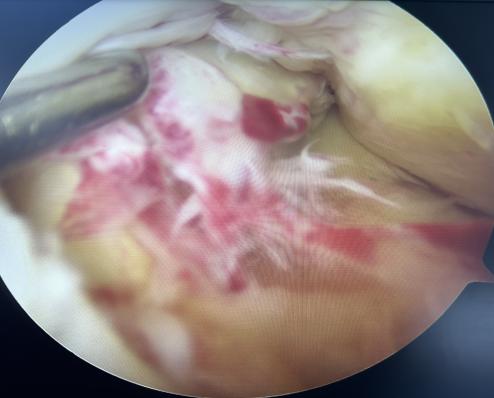

本例患者为28岁年轻女性,因意外摔伤导致左膝关节前交叉韧带完全断裂,辗转当地多家医院咨询后,最终选择前来我科手术。张智主治医师接诊患者后立即向杜恒副主任汇报,并联系尹战海主任共同讨论制定手术方案,最终确定行左膝关节镜检关节清理+半月板成形+自体腘绳肌腱重建前交叉韧带手术。

在尹战海主任的协调指导及消毒供应科的大力配合下,从总院调配关节镜设备及相关手术器械,在麻醉手术部宋珂珂、杨涵钦、李杨、高彤团队的紧密配合下,由张智主治医师主刀顺利完成手术。术后骨科任洁、孙梦媛、习姣等护理团队无缝衔接,确保了围术期无痛化管理和加速康复。术后4小时即开始无痛自主锻炼,术后1天拄拐患肢不负重活动,术后4天被动屈膝轻松达到90度,今日顺利出院继续院外康复。

2025年1月10日,我院骨科陆港院区再接再厉,单日又完成3例关节镜微创手术。分别为13岁女性外侧盘状半月板撕裂患者行半月板成形缝合修复术,为21岁男性陈旧性前交叉韧带断裂患者行自体肌腱前交叉韧带重建术,为58岁女性骨关节炎膝关节游离体患者行关节清理游离体取出术。目前这些患者均康复良好,拟于近期出院。